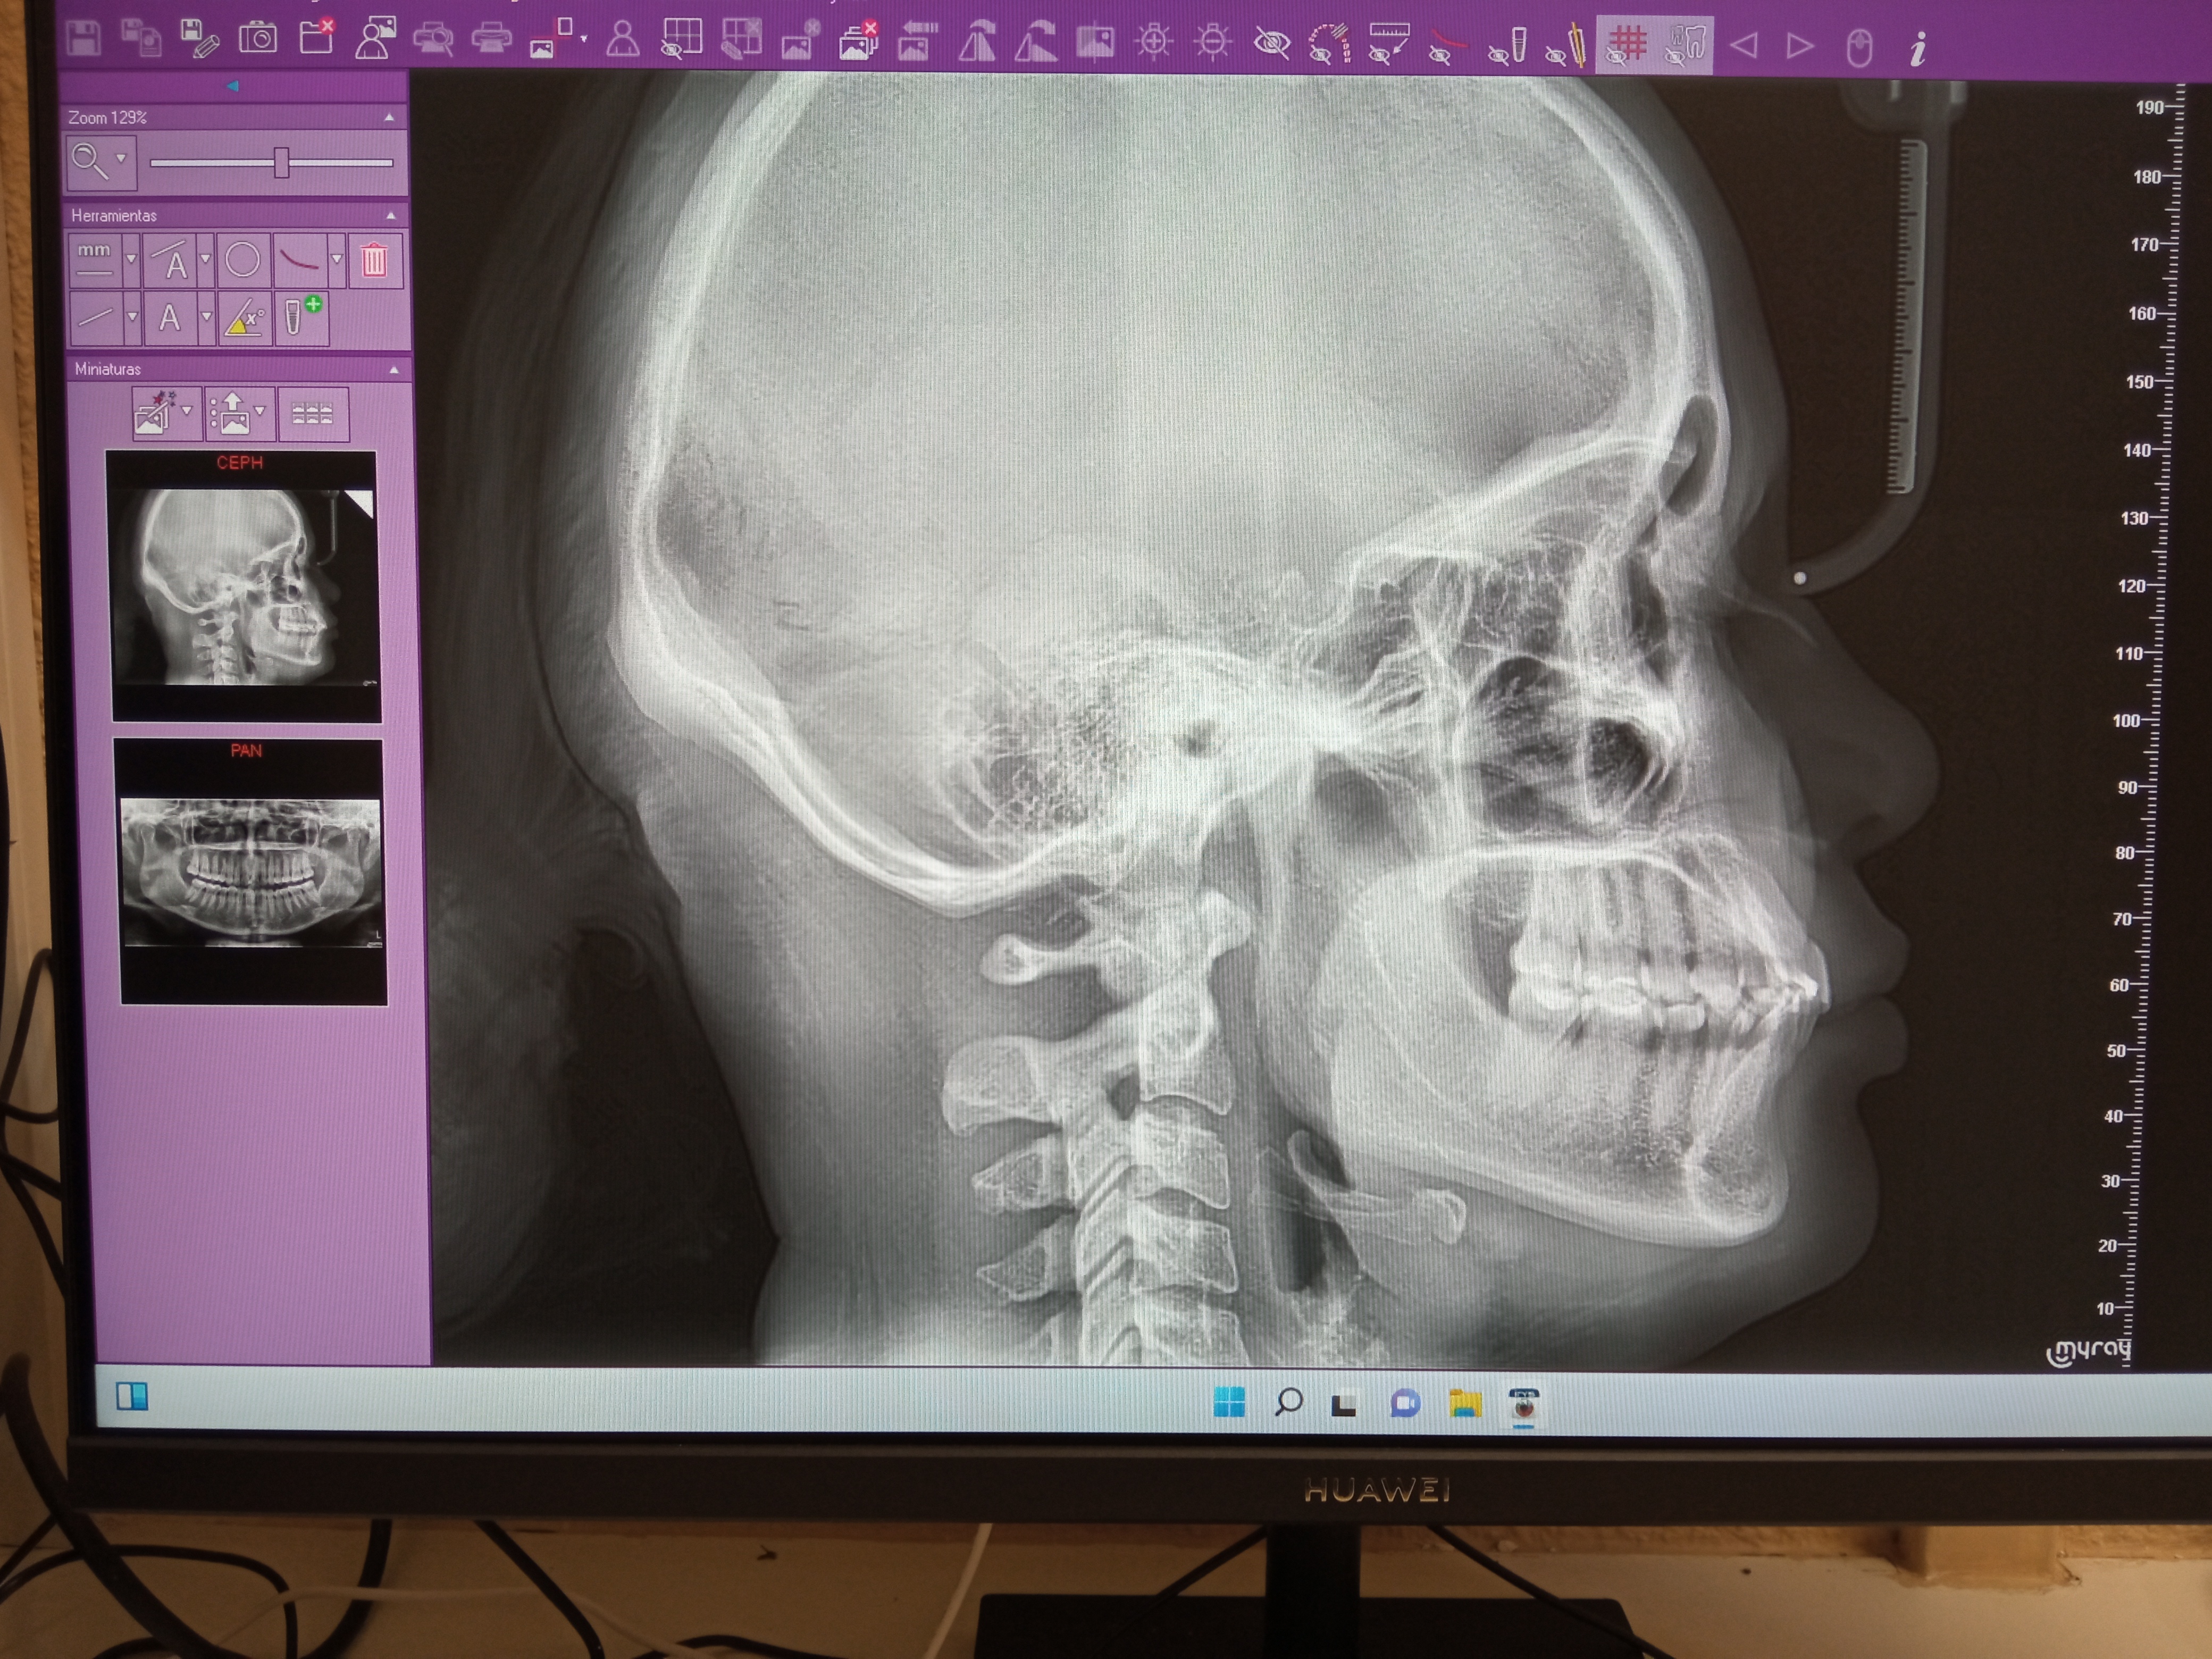

Conózcanos más en profundidad, a continuación puede observar las instalaciones donde le recibiremos